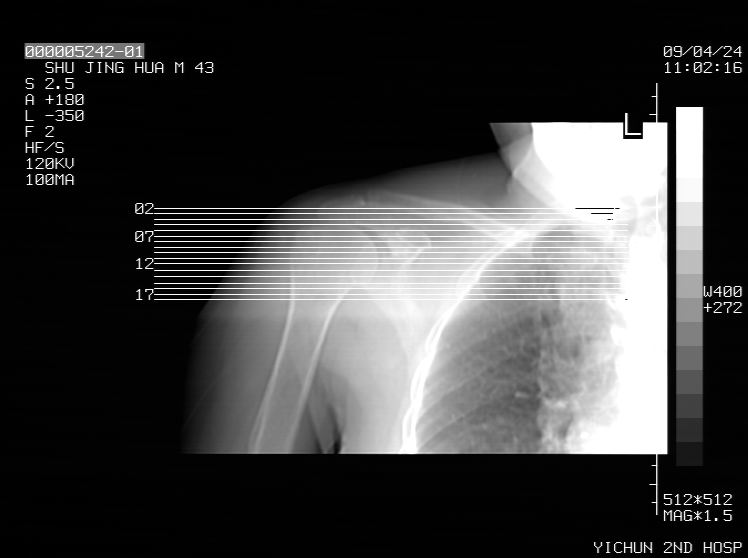

标题: CT19569:请会诊,女50岁,右肩疼痛数月 [打印本页]

标题: CT19569:请会诊,女50岁,右肩疼痛数月

钙化性肌腱炎

是指钙盐沉积在变性肌腱中的一种无菌性炎症,常见于肩关节的肩袖肌腱,引起肩部疼痛和活动受限。分为急性和慢性两种类型,急性型有肩关节突然出现急性疼痛的发作史,夜间可痛醒。